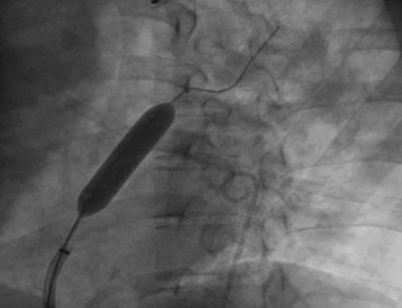

为攻克精准控制分流量的技术难题,荆志成教授带领团队采用“医工交叉”的创新研究策略。在对前期研究数据进行大量分析计算的基础上,制定了设定造口术后目标动脉血氧饱和度,计算目标分流量,再使用导管测定血流动力学参数和血氧含量数据,计算目标分流口径的策略,解决了如何精确计算患者所需要的房间隔造口的直径这一关键问题。随后,荆志成教授团队与武汉唯柯医疗科技有限公司紧密合作,设计了新型心房分流器实现精准控制分流量。同时设计了多种分流器孔径型号,且分流器设置偏心横向螺母端头,释放后可回收、可更换、可二次干预,只为用精心的设计确保经皮房间隔造口术为每一位患者带来最大获益。